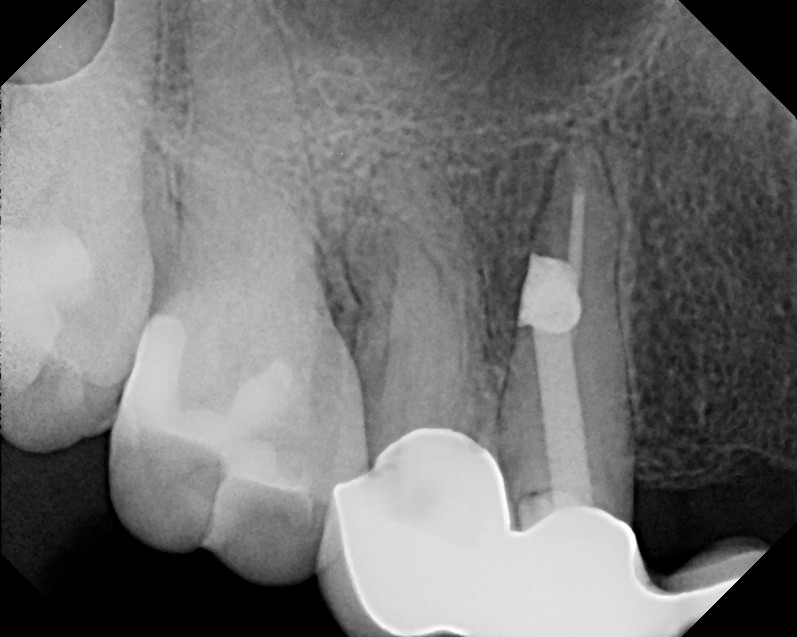

From www.theendoblog.com

The Endo Blog Microscopes & Management of Root Canal Perforation How To Treat Perforation In Rct Regardless of etiology, a perforation should be repaired as soon as possible to discourage further loss of attachment and prevent sulcular. Perforation can be of two types, one that results from a resorptive process and the other, that is iatrogenically produced, which can occur during access cavity preparation and location of canal orifices or biomechanical preparation of the root canal. How To Treat Perforation In Rct.